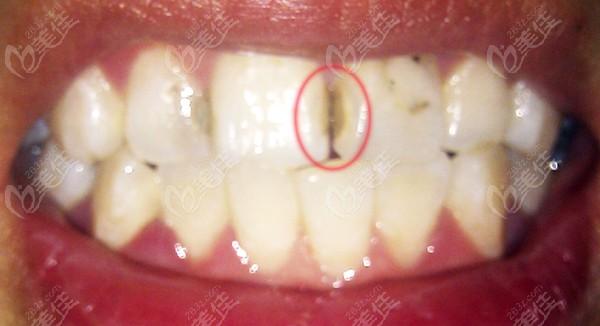

2. 为什么牙齿根尖术后会发黑?

牙齿根尖术后发黑是因为手术过程中使用的药物会对牙齿造成影响。这些药物中的氧化铁颗粒在手术后会残留在牙齿内部,随着时间的推移,会逐渐转化为黑色物质,从而导致牙齿变黑。